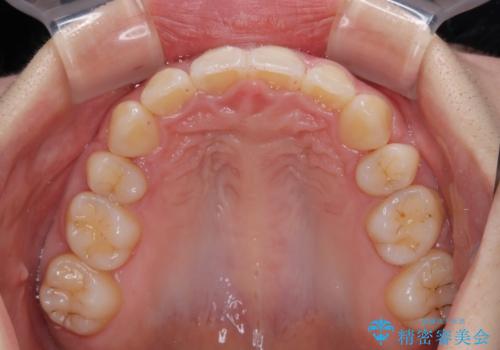

順調に治療が進み、2年弱で想定していたとおりの仕上がりにて治療を終えることができました。

- 下唇に跡がつくほどに飛び出した上顎前歯を気にして来院された患者様です。

来院された時から4本の抜歯が必要であることを理解されていらしており、通法通り上下左右の第一小臼歯4本を抜歯し、ワイヤー装置にて矯正治療を行うこととしました。